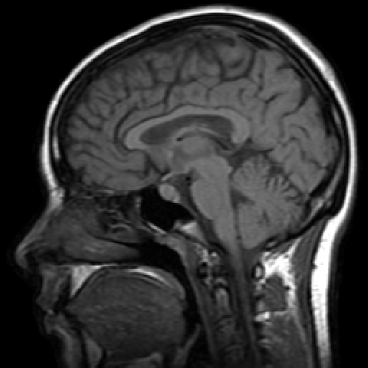

Typically the structural component contains the main components of the image, which is represented by the lower frequencies. The textural component contains the finer details like edges or high oscillations. These components are included in the high frequencies of an image. Therefore we introduce the Riesz potential, which captures the high frequencies, as the inverse of the fractional Laplacian. In Figure 1 we illustrate a decomposition into these components. This paper contains two main results. First we derive a rigourous error estimate for the bilevel problem in the case of spectral approximation. The numerical realization is easy to implement and in comparison to the ROF model much faster. Second we introduce a new image decomposition model, which has promising results in simultaneous image denoising and decomposition. To the best of our knowledge, this is the first work using fractional models in image decomposition. Moreover, we point out, that fractional differential operators are applicable in case of image denoising and decompositon. The use of fractional diffential operators in other image processing areas is a point of future research.